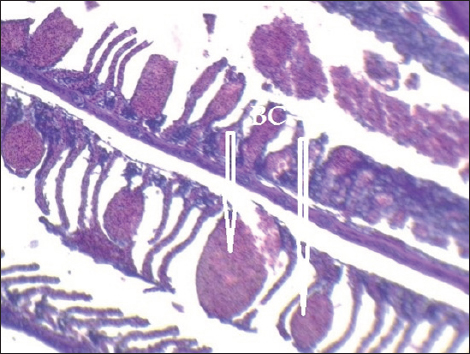

Histopathological findings of gill section showed telangictatisis and epithelial lifting in secondary lamellae (Fig. 7) with hemorrhage and blood congestion (Fig. 8), also, the result showed the central venous dilation with blood congestion and epithelium hyperplasia with complete fusion of the secondary lamellae (Figs. 9 and 10) and edema in the filamentary epithelium (Fig. 11) in addition to mononuclear cells infiltration (Figs. 12 and 13).

Fig. 8. Histopathological sections of gill of C. carpio showing severe telangiectasia in secondary lamellae with hemorrhage and blood congestion (BC) (H&E X10).

The changes in gill tissue are not exclusive to As, Pb, and Hg toxicity (e.g., telangiectasis, epithelial lifting, hemorrhage, congestion, etc.) which have been previously reported in other stressful situations, like pesticide exposure (Fanta et al., 2003). All of these changes may be defense mechanisms meant to lengthen the time it takes for waterborne contaminants to diffuse and enter the bloodstream (Arellano et al., 1999). With particular reference to exposure to metals, Mustafa et al. (2012) observed telangiectasis, necrosis, in mirror carp C. carpio exposed to Cu, with the epithelium lifted away from the basement membrane. Similar results were also noted in Sole senegalensis, the Senegalese sole, after it was exposed to a sub-lethal concentration of Cu for 7 days (Arellano et al., 1999).